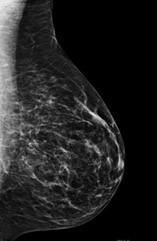

Like a screening mammogram, diagnostic digital mammography takes X-rays of the breast. Additional views of the area of concern are performed with different types of compression or magnification.

Mammograms can show changes in the breast tissue before a patient or physician can feel them, regardless of breast size. Our skilled breast technologists utilize special equipment to obtain the best possible imaging of each woman’s breast tissue, regardless of size or shape.